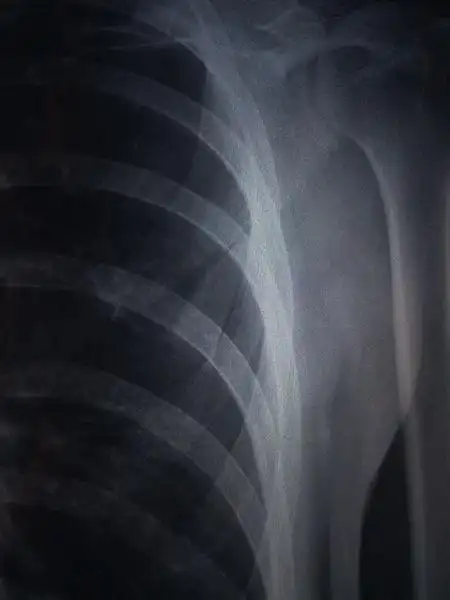

求骨科大夫帮助,肩胛骨下角骨骨折,求帮助,求指导